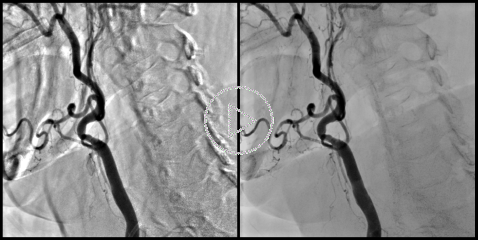

Motion Compensated DSA:

Motion Compensated DSA essentially uses the same algorithms as the Cardiac DSA. Elastic registration of the subtraction mask allows for substantial reduction of motion artifacts. The images on the left show a comparison between the "classic" (rigid) DSA without motion compensation (left image) and the Motion Compensated DSA (right image). Both images were produced with suppression of the "background" anatomy set to 75%. |